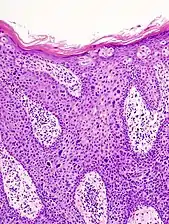

Bowen's disease is essentially equivalent to and used interchangeably with SCC in situ, when not having invaded through the basement membrane.[33] Depending on source, it is classified as precancerous[34] or SCC in situ (technically cancerous but non-invasive).[35][36] In SCC in situ (Bowen's disease), atypical squamous cells proliferate through the whole thickness of the epidermis.[33] The entire tumor is confined to the epidermis and does not invade into the dermis.[33] The cells are often highly atypical under the microscope, and may in fact look more unusual than the cells of some invasive squamous cell carcinomas.[33]

SCC in situ, high magnification, demonstrating an intact basement membrane.[33]